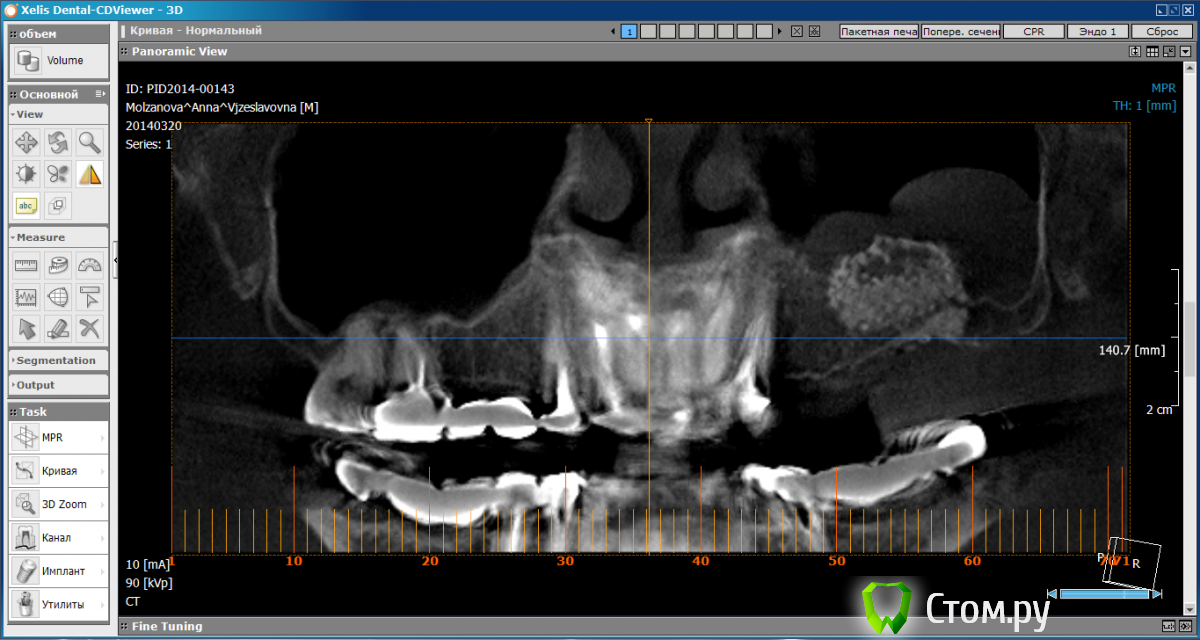

Анна2604 Опубликовано 30 апреля, 2014 Поделиться Опубликовано 30 апреля, 2014 Здравствуйте! Было:11.09.13г был сделан синус-лифтинг гранулами Bio-oss с мембраной Bio-Gide. 20.03.14г сделала КТ (один из скриншотов) Планировалось поставить импланты на 24 и 26 зубы, на них одеть мост.По личным причинам делать импланты там, где делала синус-лифтинг, не могу. Сейчас нужно выбрать систему имплантов. Предлагают Astra Tech цена:хирургия 2*25000ортопедия (д\о под м\к на импланте 6000, хирург шаблон 2*4500, м\к на импл 2*7300)аппаратура (абатмент, колпачек, винт фиксирующий, дублер импланта, дублер абатмента, полувыжигающий цилиндр) - 2*11500Итого 102600 Bicon по цене приблизительно так жеТе, кто предлагают астру, будут делать и коронки потом. Клиника частная, новая, хорошо оборудованная. Врачи молодые , отзывов нашла немного. Но очень подробно все расписывают и рассказывают. Все делают "под ключ" Байкон ставят при медакадемии, ставит КМНВ кабинете (на мой непрофессиональный взгляд) техника супер- над креслом большой экран, да и само кресло впечатлило.Но - сплошной поток, ничего не объясняют, не разговаривают, точную сумму, и что в нее входит - не озвучивают (типа не более 110 тыс). Коронки на импланты сами не делают, предлагают любых штатных ортопедов медакадемии. Скажите, пожалуйста:- Верно ли , что у байкона проблемы как раз с последующей ортопедией и что лучше делать все у одних врачей, чтобы потом не было вопросов?- Верно ли, что клин Морзе предпочтительнее винтовым системам по дальнейшей резорбции кости?- Может быть мне поискать другой имплант (тогда какой?) - Может быть мне поискать другую клинику? (г. Тверь)? Заранее спасибо! Вот все скриншоты http://s45.radikal.ru/i109/1404/ed/7914bf97071d.jpghttp://s020.radikal.ru/i718/1404/63/978a89c63f56.jpghttp://s006.radikal.ru/i213/1404/f0/eaea91b5be6d.jpghttp://s018.radikal.ru/i517/1404/60/a8e87845206f.jpghttp://i069.radikal.ru/1404/88/7ca7b5c3a637.jpghttp://s020.radikal.ru/i719/1404/1a/76d7b5cef90f.jpghttp://s005.radikal.ru/i210/1404/ef/198ca22d480f.jpghttp://s020.radikal.ru/i715/1404/74/9464c878c220.jpghttp://s013.radikal.ru/i323/1404/4d/18b7b836d34d.jpghttp://s006.radikal.ru/i215/1404/10/54d1647e1ba1.jpghttp://s020.radikal.ru/i711/1404/d5/9113f8dfa2d2.jpghttp://s018.radikal.ru/i521/1404/f0/0771efa96d27.jpghttp://i031.radikal.ru/1404/15/092c47924b68.jpghttp://s57.radikal.ru/i156/1404/fb/bf5004d99d40.jpghttp://i047.radikal.ru/1404/f9/d2e5ac315899.jpghttp://i056.radikal.ru/1404/9f/f66090e230f3.jpghttp://s005.radikal.ru/i212/1404/65/5aa4a83e143c.jpg Ссылка на комментарий